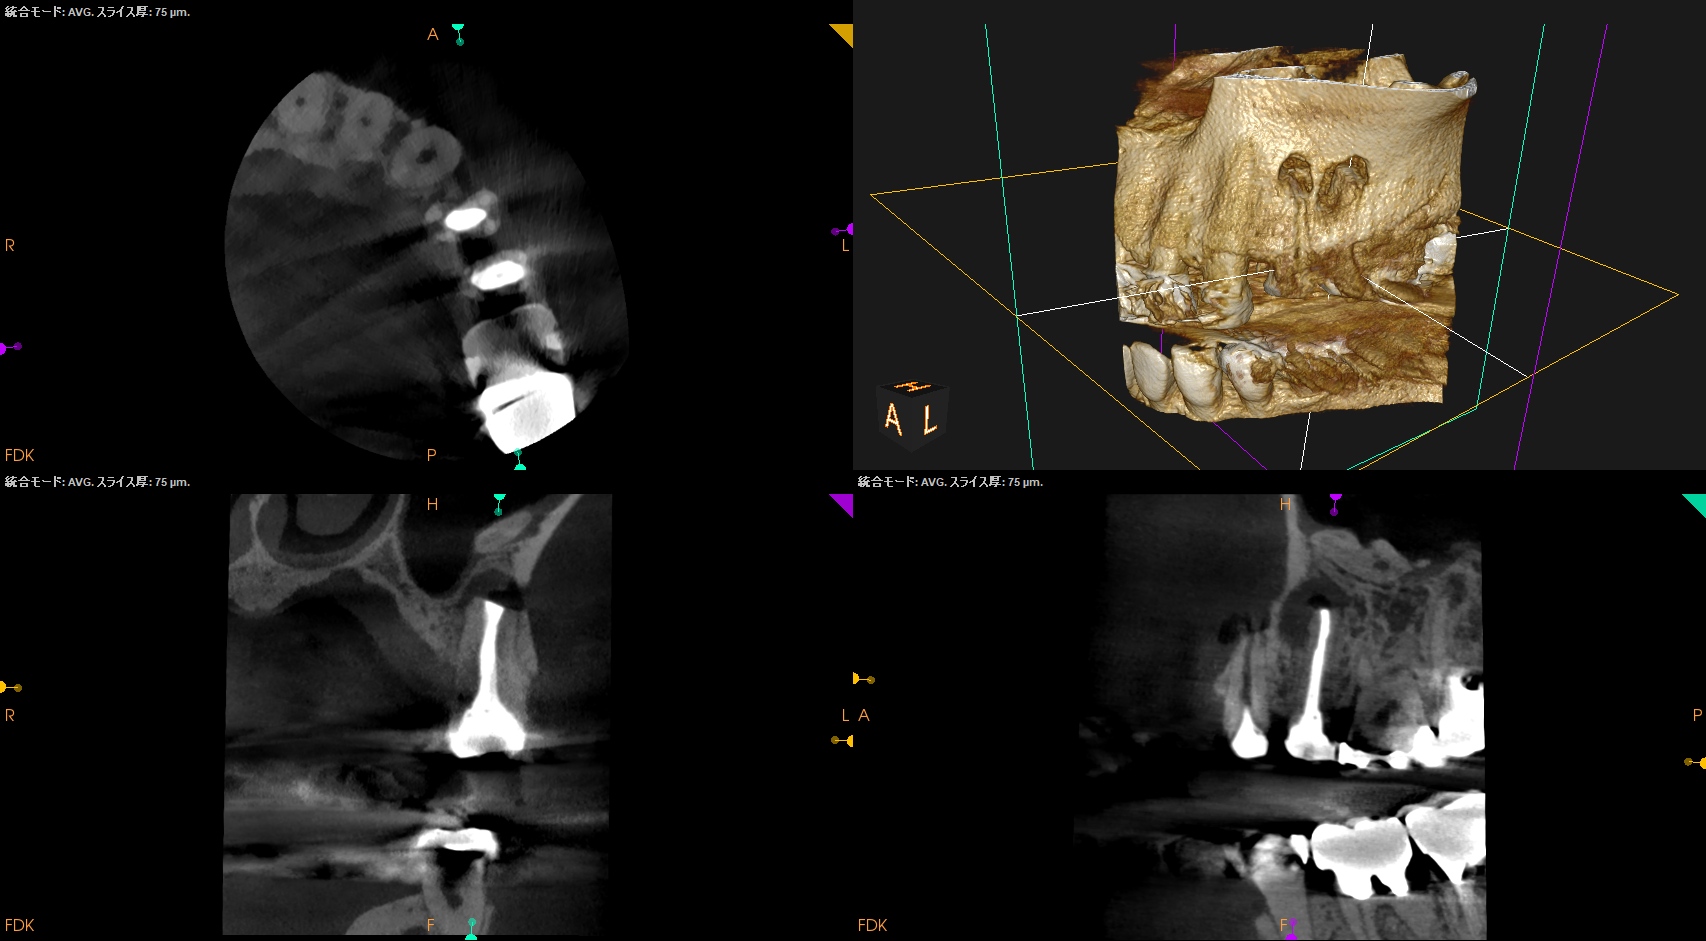

CBCT(2025.8.25)

#12 B

#12 P

#13